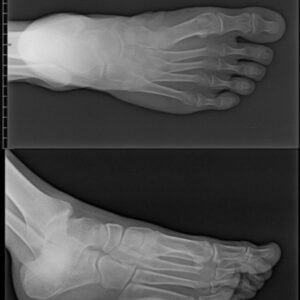

Radiografía de pie sin alteraciones óseas identificables. El cultivo de la lesión reporta colonias de crecimiento lento, secas, rugosas con aspecto aterciopelado de color crema compatibles con Nocardia Sp.

Figura 5.- Radiografía de pie, sin evidencia de imágenes osteolíticas.